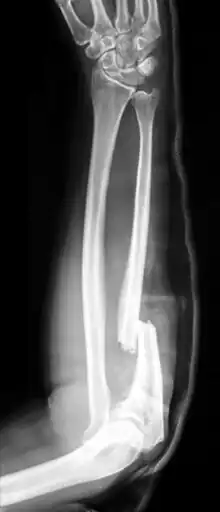

Monteggia fracture-dislocation

X-ray of Monteggia fracture of right forearm

The Monteggia fracture is a fracture of the proximal third of the ulna with dislocation of the proximal head of the radius. It is named after Giovanni Battista Monteggia.[1][2]